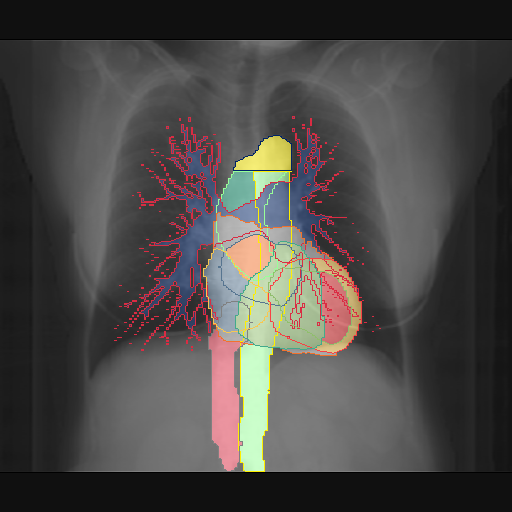

We show qualitative results for frontal projections in Fig. 2. We show a subset of classes belonging to the supercategories lungs, vascular systems, bones, and abdomen/digestive system. The predictions show minor deviations at the boundaries of the individual classes of the respiratory and vasculature system, while some inaccuracies become visible in the abdominal area. The qualitative results for the lateral projections are displayed in Fig. 2. Akin to the frontal view, the predictions show smoother borders but align with the ground truth. Apart from this, the segmentations provide matching insights on the thoracic anatomy with a slight deviation from the ground truth for both frontal and lateral views.

Fig. 2 shows quantitative segmentation results for frontal (top row) and lateral (bottom row) views. We display the class performances in the form of IoU (left), DICE (center), and Hausdorff distance (right) for each sample as a scatter plot with the mean performance for the classes shown by a line plot. Generally, we see performances for standard spinal classes, such as the thoracic vertebrae with average IoU-scores above 80%, while the average performance of rare vertebrae of the dataset belonging to the cervical and lumbar spine can drop down to 40%. In the frontal view, there exists more variance in thoracic vertebrae segmentation performance compared to the lateral view. Bone structures such as the sternum, clavicles, and scapula achieve IoUs in the mean from 85% to 95%. For ribs, we can see a noticeable performance drop for the anterior parts of the lower ribs independent of the side. The lower anterior ribs typically do not contain a large area, making them difficult to segment. This behavior is mirrored in the lateral view across the metrics. Abdominal classes can vary in segmentation quality as they occur in a nearly homogenous region. For example, while the liver or stomach are typically well-segmented, the duodenum and kidneys are more complex. Heart and Lung related classes show near-perfect segmentations with scores above 90% IoU. Breast tissue segmentation in comparison only achieves a mean of 70% mIoU. It can be noted that classes in the lateral view tend to have slightly better scores than their frontal counterparts.

We display qualitative results in Fig. 3. The annotators tend to be content with most annotations. There are edits at the extensions of the esophagus, trachea, and aorta and corrections of the lower ribs. There is little consensus for classes in the abdominal area, such as the stomach, as seen on the right of Fig. 3 . In contrast, the annotators often align for bone classes.

We show the quantitative segmentation performance against medical expert annotations for all classes in Fig. 3 . The dashed lines represent the IAA, whereas the dotted line displays the average MAA. As the task for the human annotators was not to annotate from scratch but to correct wrong pixel-wise predictions, we can see a high MAA for most classes. In the frontal view, the most significant disagreements exist for rare bone structures such as L3 and C4, lower ribs, the mediastinal distribution, or the breast tissue. The IAA and MAA are highly similar with mIoU of respective 95% and 94%. The Hausdorff distance for MAA is slightly lower than the IAA, indicating slight differences in boundary annotations while maintaining a considerable overlap with the other annotator. In the lateral view, the concrete delineation of rib structures appears ambiguous, leading to lower MAA and IAA with a greater IAA than MAA for all metrics in this supercategory. Overall there is less agreement between the medical experts in the lateral view, leading to a better average MAA than IAA across all metrics (i.e. 85% vs 83% mIoU). While the experts propose changes to the original predictions, they are often not overlapping. In the lateral view, rib segmentations can become quite hard to interpret. While both annotators disagree with the rib segmentations, they do not always agree on how they should look. Similarly to the frontal view, tube-like structures like the esophagus are extended as they can appear fractured at times.